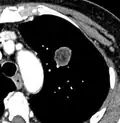

Chest X-ray showing a solitary pulmonary nodule (indicated by a black box) in the left upper lobe.